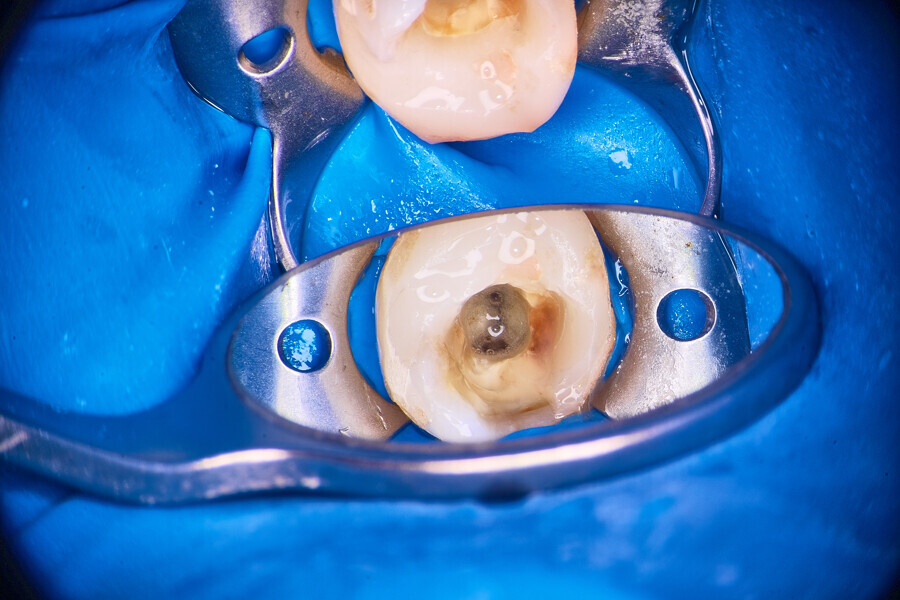

Under local anaesthesia, a dental dam was placed, and the field was sealed with liquid dental dam (RUBBER-DAM liquid, CERKAMED; Fig. 2). The temporary restoration was removed. The pulp chamber was irrigated with distilled water and sodium hypochlorite 5,25% activated with ultrasonic tips (Fig. 3). The first mesiobuccal (MB1), DB and palatal (P) canals were patent, so I was able to establish the working length with the C-PILOT file (VDW) and an apex locator (E-PEX, Eighteeth). The canals were shaped up to approximately two-thirds of the working length with the 25/0.07 Perfect Shape reciprocating file (Shenzhen Perfect Medical Instruments). The dentine above the orifice of the MB2 canal was removed using a diamond-coated ultrasonic tip (ED3D, Woodpecker), revealing an isthmus located between the MB1 and MB2 canals. Preparation of the orifice of the MB2 canal was possible only in the coronal third with a hand file (Fig. 4). The isthmus between both canals was removed for an additional 2 mm in depth also with the diamond-coated tips (Fig. 5).

Fig. 2

Fig. 3

Fig. 4

Fig. 5

Fig. 6